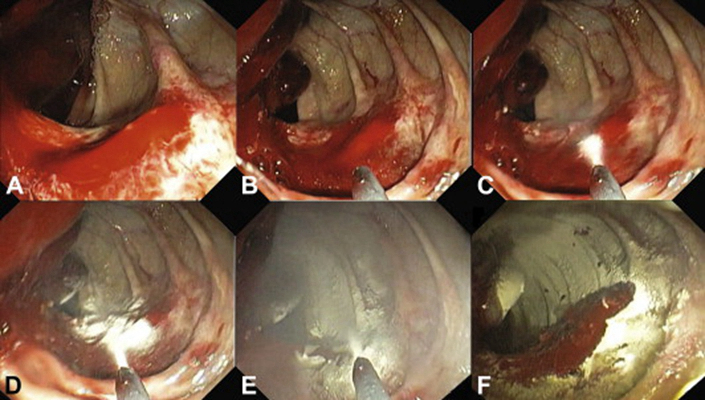

結腸癌症狀 (42)

結腸癌症狀 (43)

結腸癌症狀 (44)

結腸癌症狀 (45)

結腸癌症狀 (46)

結腸癌症狀 (47)

結腸癌症狀 (48)